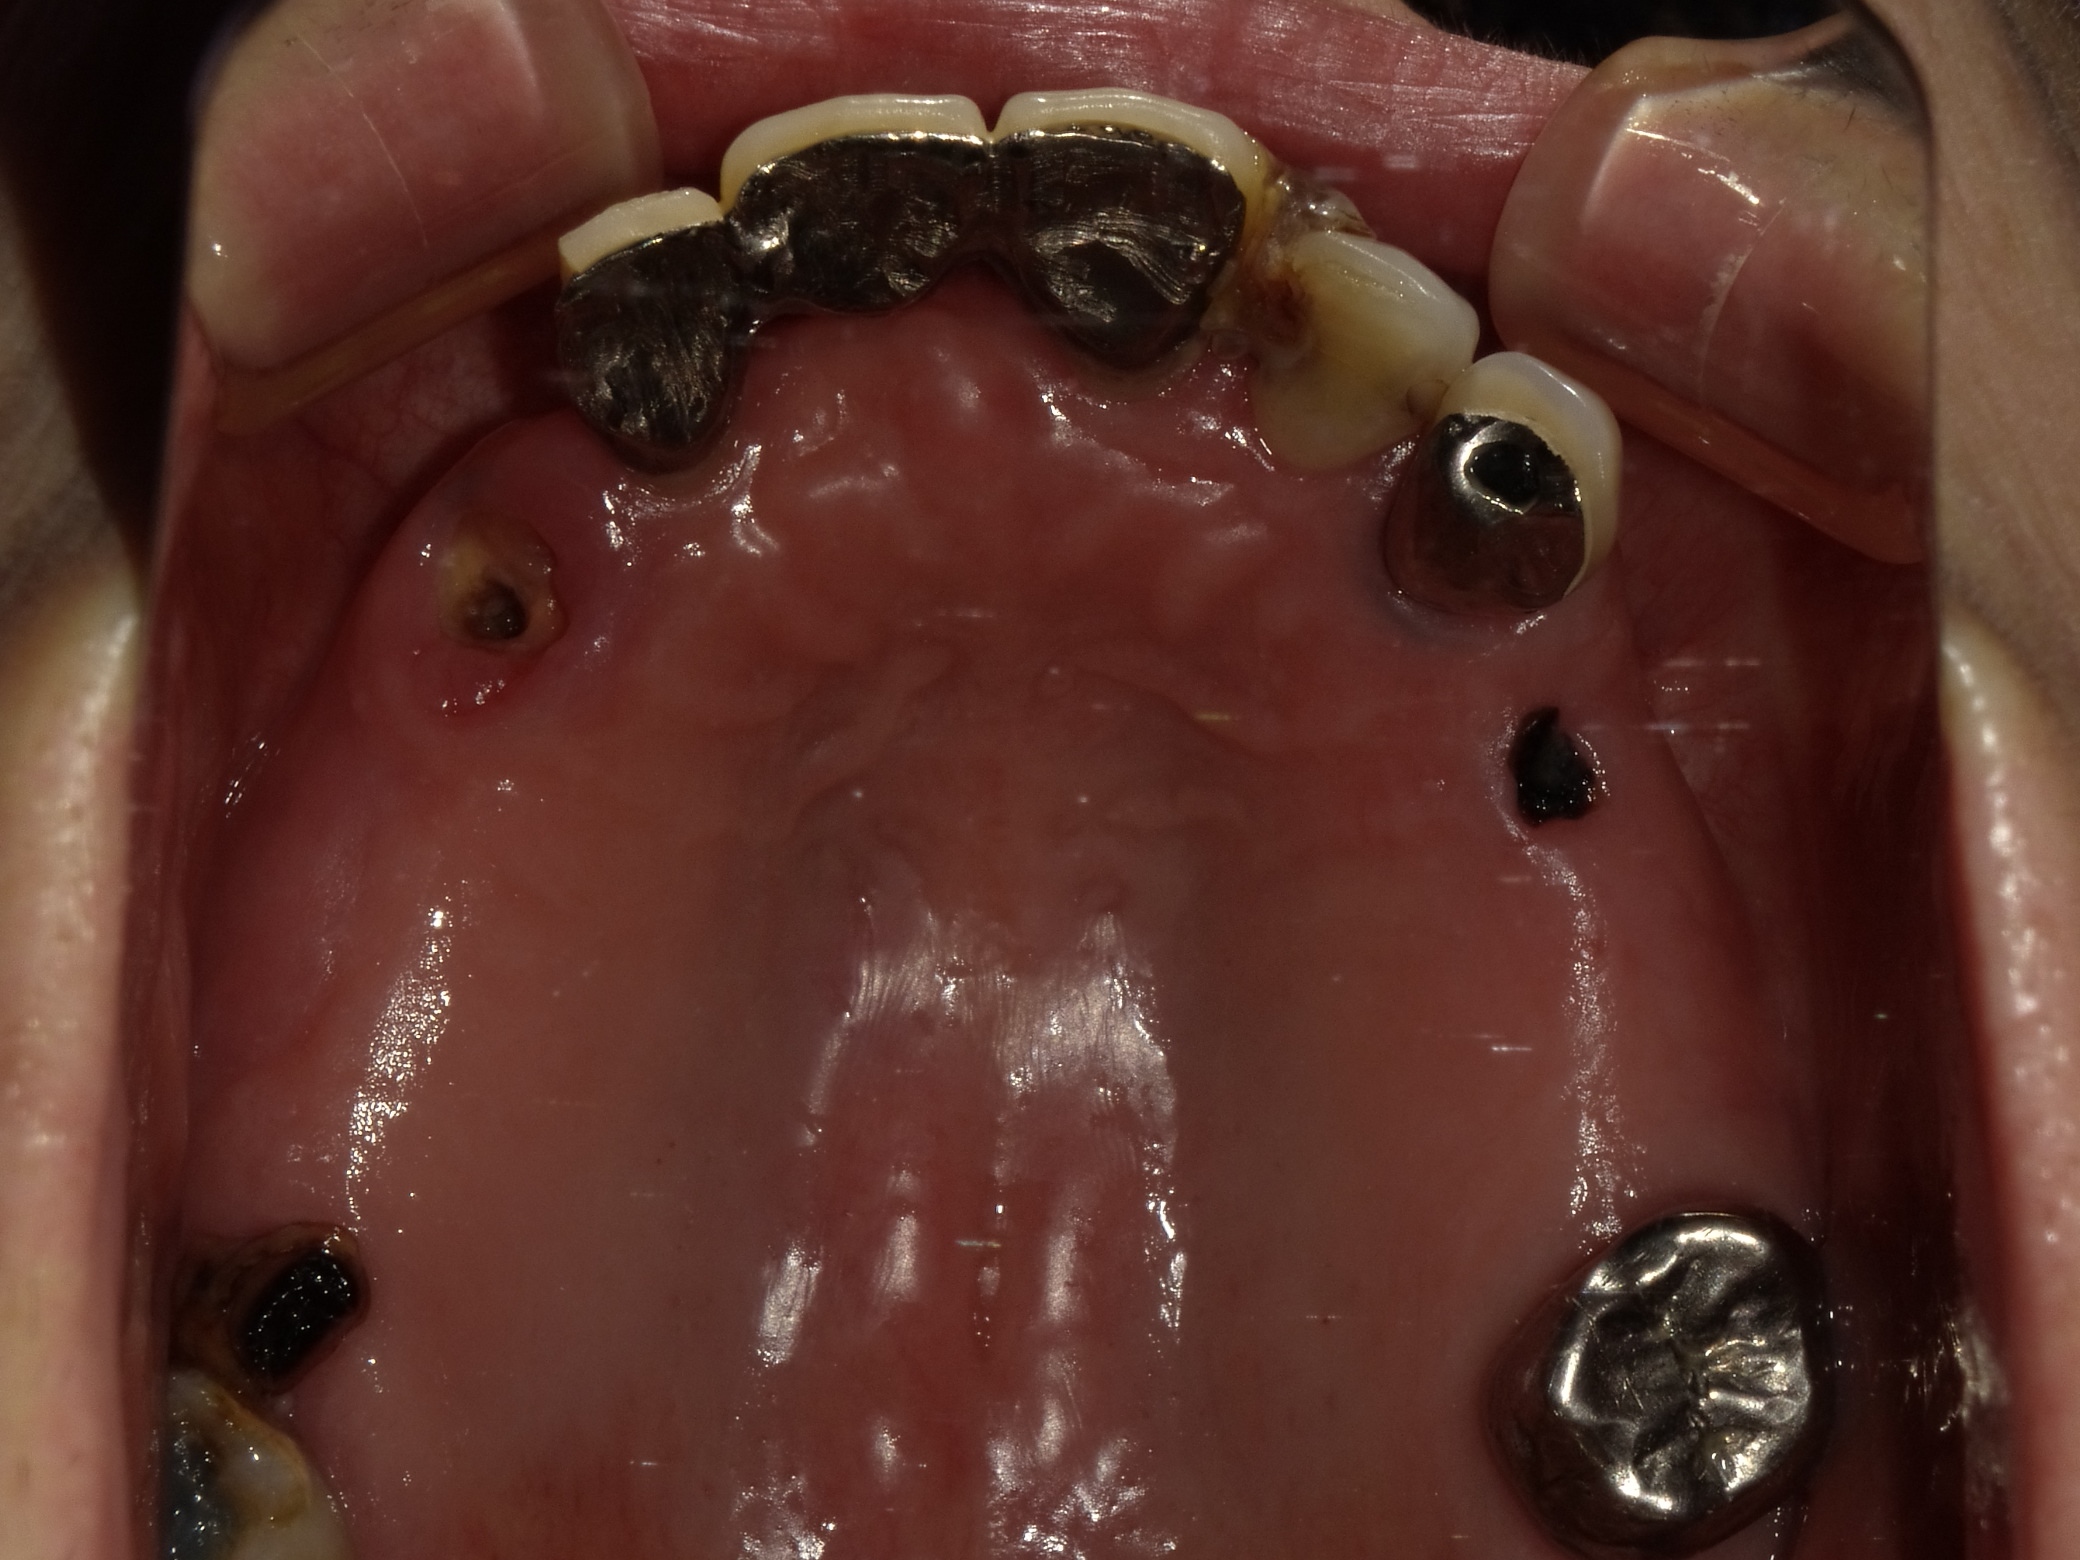

BEFORE

主訴

全体的に見た目を綺麗にしたい。奥歯でしっかり噛みたい。

診断名・主な症状

臼歯部欠損

年齢

70歳

治療内容

インプラント埋入(右上4・6,左上4・6,右下6,左下6)

ジルコニアBr(右上3―左上3)

ジルコニア(右下5,左下5)

治療期間/

通院回数

インプラント 1年5ヶ月/13回

ジルコニアBr、ジルコニアクラウン 3ヶ月/10回

費用

インプラント: 2,552,000円

その他治療: 640,000円

合計 3,192,000円

*いずれも税込